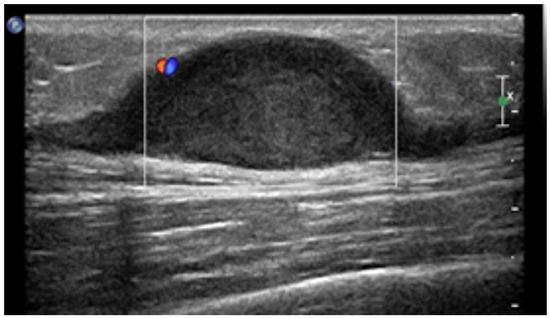

- Leiomyosarcomas: seen on the abdominal wall as either a primary process or as an extension of an intra-abdominal process [23,24]. Leiomyosarcomas demonstrate heterogeneous attenuation and signal intensity, with irregular peripheral enhancement and enhancing solid portions, mixed with hemorrhagic and necrotic areas [24]. Fatty components are absent (Figure 9) [23,24].